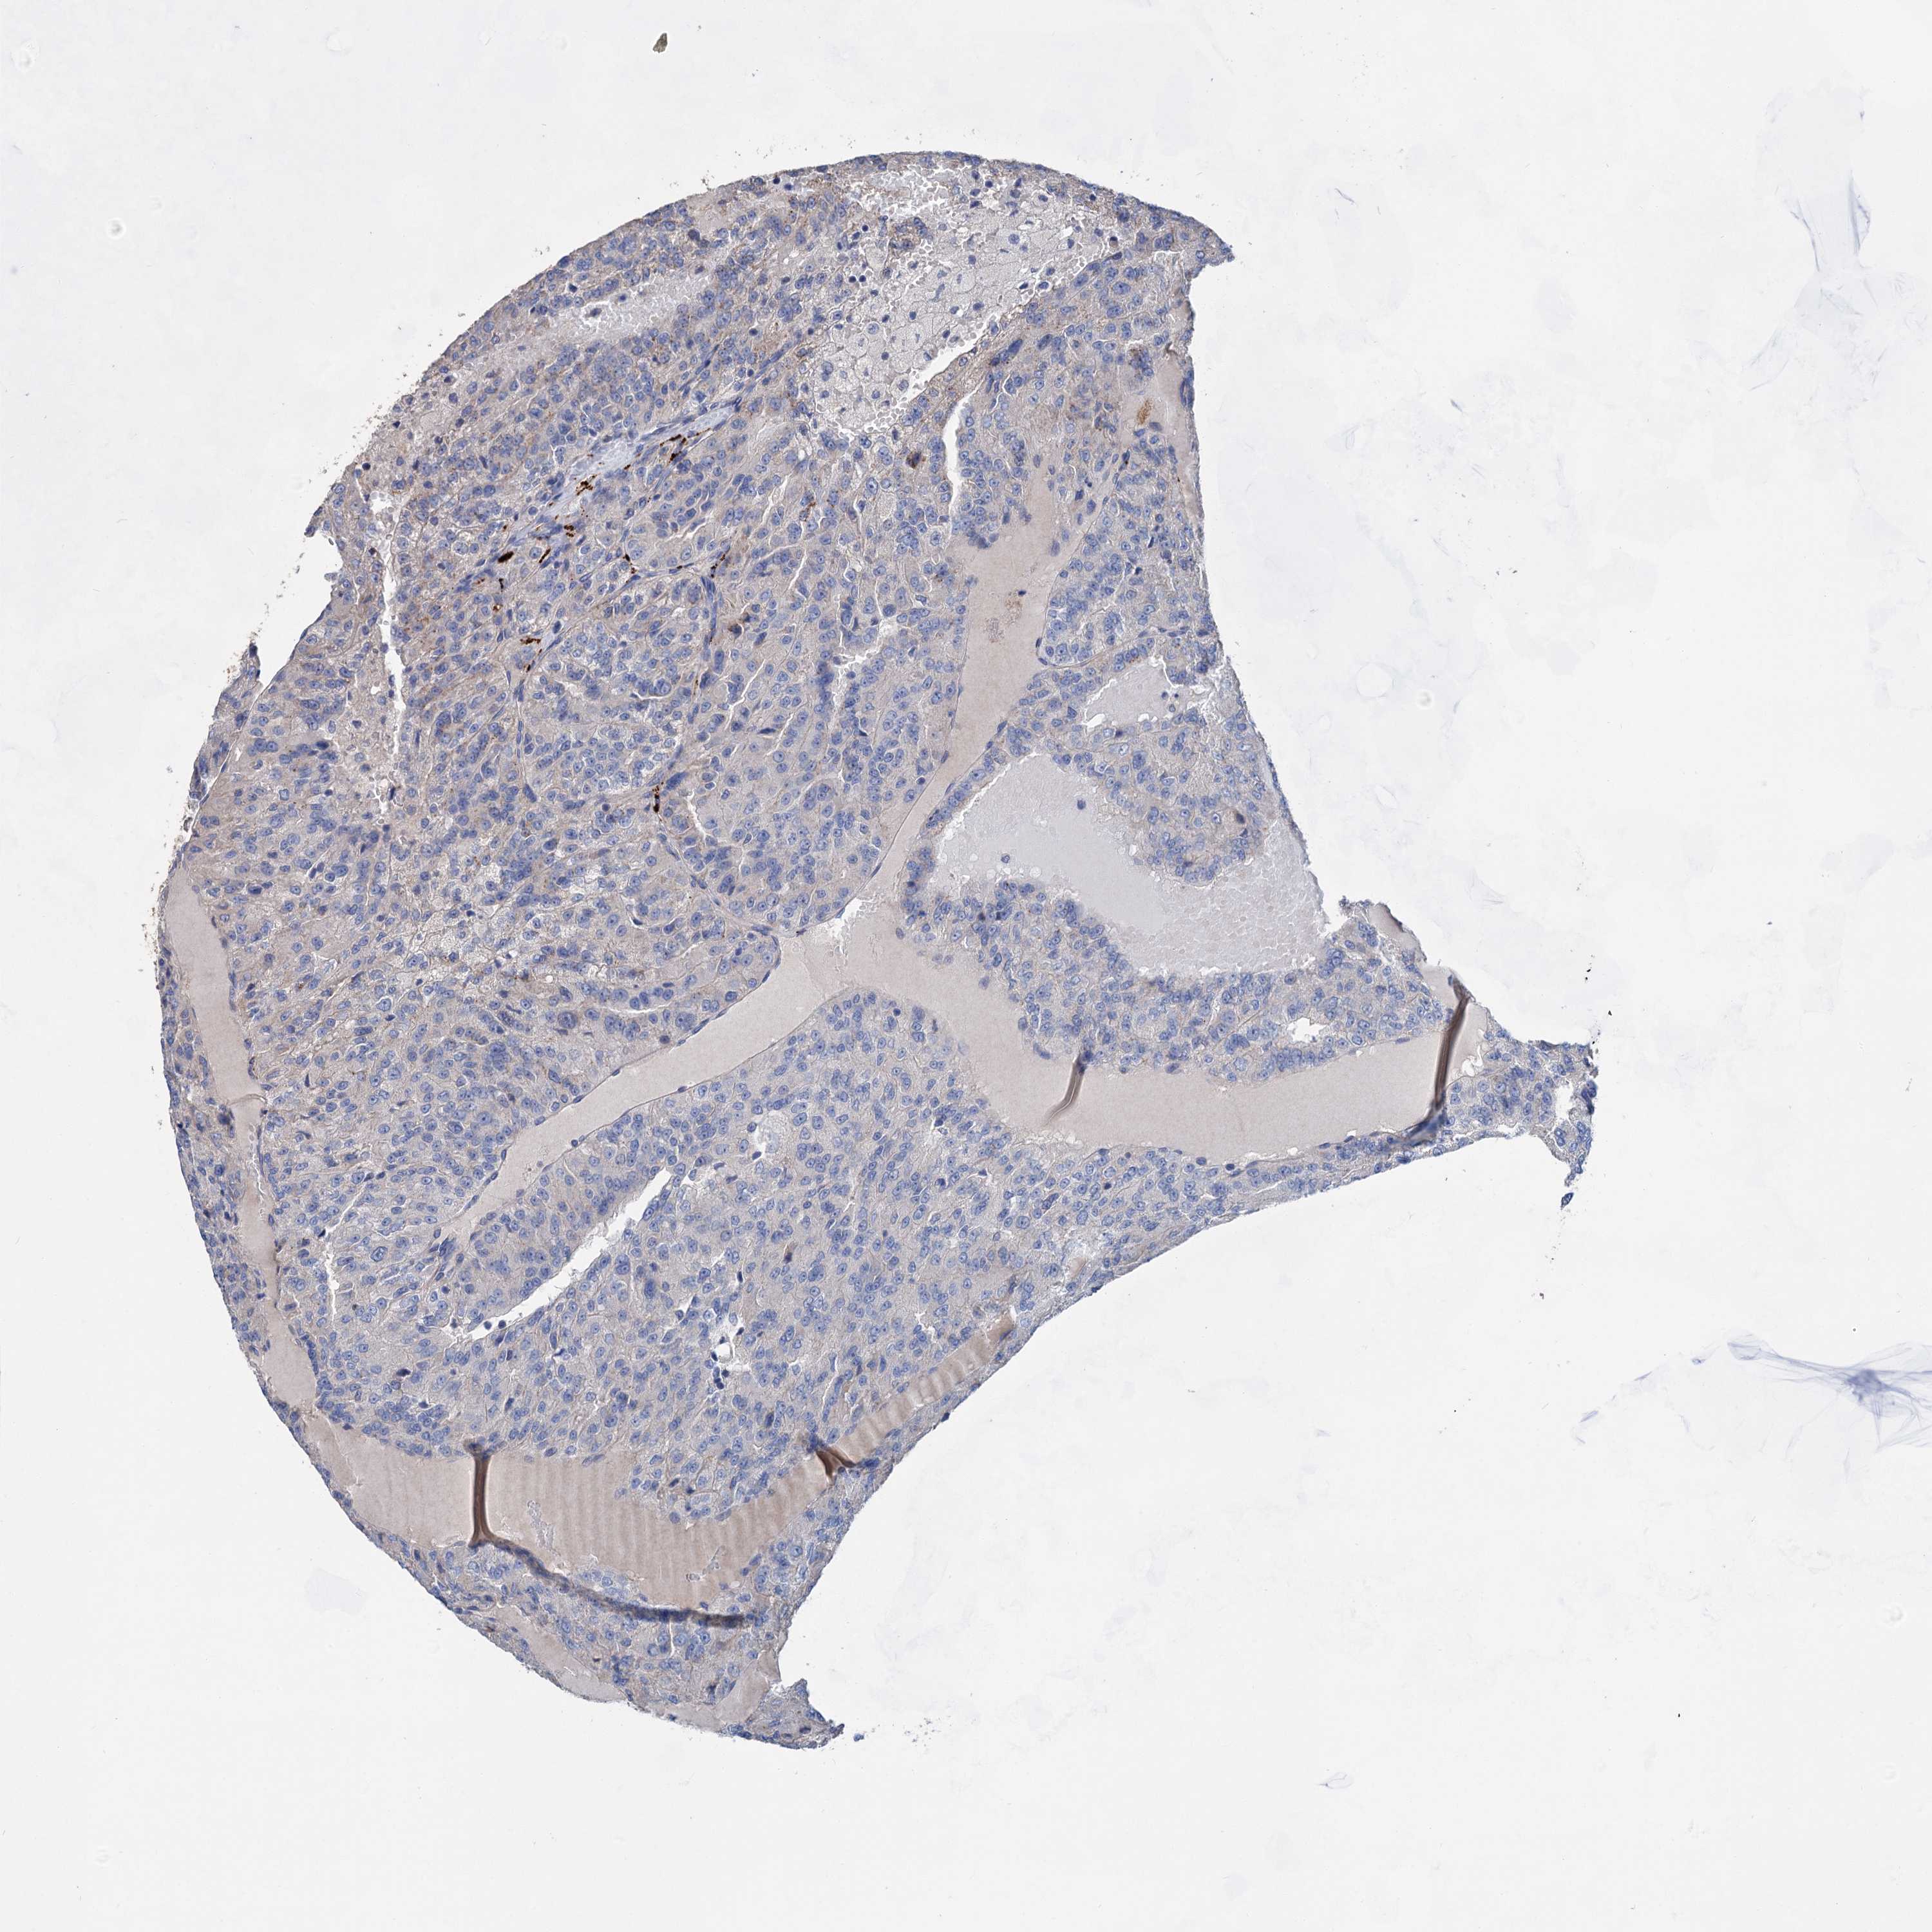

CANCER RENAL CANCER Show tissue menu

KICH TCGA KIRC TCGA KIRC VALIDATION KIRP TCGA PROTEIN RCC CPTAC PROTEIN EXPRESSION

Renal cancer

Kidney chromophobe

KIDNEY CHROMOPHOBE (TCGA) - Interactive survival scatter ploti

GPR155 is not prognostic in Kidney Chromophobe (TCGA)